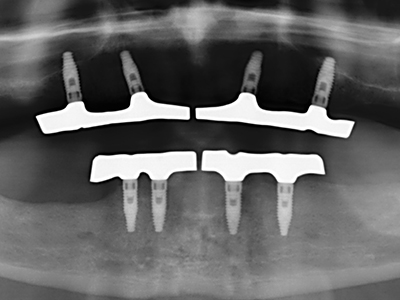

Die Präparation des lateralen Fensters bei der externen Sinusbodenelevation stellt gerade für chirurgisch unerfahrene Implantologen eine große Herausforderung dar. Die knöcherne Bedeckung der Kieferhöhle ohne eine Verletzung der darunterliegenden Schneider’schen Membran abzutragen ist dabei nur ein Teil der Operation – nach Schaffung eines ausreichenden Zugangs muss die Kieferhöhlenschleimhaut vorsichtig mobilisiert werden, um Raum für das einzubringende Material bzw. die Implantate zu schaffen. In dieser Indikation ist die Piezochirurgie zweierlei hilfreich: zum einen kann durch Verwendung diamantierter Instrumente eine selektive Knochenabtragung erfolgen und die darunter liegende Schleimhaut bleibt bei vorsichtiger Vorgehensweise intakt. Zum anderen unterstützen die Ultraschallfrequenzen zusätzlich eine komplikationslose Ablösung der Schleimhaut – sie werden durch spezielle stumpfe Ansätze in den Spaltraum zwischen Schleimhaut und Kieferhöhlenboden übertragen (Cassetta, Ricci et al. 2012, Pereira, Gealh et al. 2014) (Rickert, Vissink et al. 2013). So erscheint es nicht verwunderlich, dass in aktuellen Übersichtsarbeiten über die externe Sinusbodenelevation neben der Verwendung von rauen Implantatoberflächen und dem Einsatz von Knochenersatzmaterialien auch der Einsatz von piezoelektronischen Geräten als positiv bewertet wird (Wallace, Tarnow et al. 2012).

Wie sich in der Vergangenheit gezeigt hat stellt prinzipiell jeder knochenchirurgische Eingriff eine mögliche Indikation für die Piezochirurgie dar. So lässt sich die Präparation des mobilen Segmentes bei der Distraktionsosteogenese (Abb. 23-25) und der Sandwichosteotomie mit speziellen Ansätzen bewerkstelligen, ohne die für den Erfolg beider Techniken essenzielle Blutversorgung des krestalen Anteils zu gefährden (Gonzalez-Garcia, Diniz-Freitas et al. 2008).

Weitere Einsatzgebiete ergeben sich in der Kieferhöhlenchirurgie: Hier können nach konzentrischer Präparation eines in der Regel trapezförmigen Knochendeckels der fazialen Kieferhöhlenwand Pathologien und Fremdkörper aus der Kieferhöhle entfernt werden. Der Knochendeckel wird nach Abschluss des intra-antralen Operationsanteils reponiert und durch Verkeilen oder adaptierende Nähte gegen Dislokation gesichert.